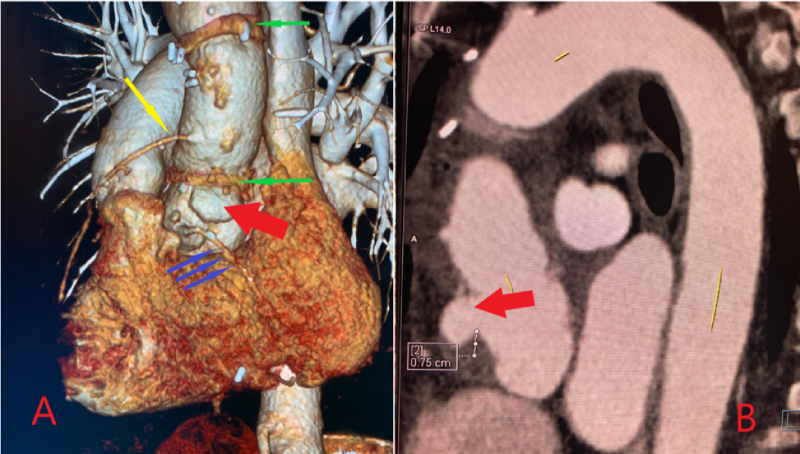

A 56-year-old Caucasian woman with a history of active tobacco abuse, systemic lupus erythematosus, and hypothyroidism underwent emergent surgical repair of a Stanford type A aortic dissection with a 28 mm Gelweave graft. Her aortic valve was intact and did not require repair. She also underwent empiric aortocoronary bypass with saphenous vein grafting to the left anterior descending artery (LAD). Her recovery was slow, and her hospital course was prolonged, but she was eventually discharged home. One-month routine follow-up computer topography angiography (CTA) of her aorta demonstrated that a pseudoaneurysm had developed at the suture site along the anterior aspect of the ascending thoracic aorta, above the right coronary cusp (Figure 1A and Figure 1B). The patient was referred to the heart clinic for further management.

The patient was evaluated by our Structural Heart Team, and her computed topography (CT) scan was reviewed at our Multidisciplinary Structural Conference. Her CT demonstrated a pseudoaneurysm located at the proximal suture site, along the anterior aspect of the ascending thoracic aorta, just above the right coronary cusp (Figure 1A and Figure 1B). The neck of the pseudoaneurysm was 9.5 mm (Figure 2A), the depth was 16.5 mm (Figure 2B), and the side-to-side diameter was 21.2 mm (Figure 2C). The distance of the right coronary artery (RCA) ostium from the neck of the pseudoaneurysm sac was 7.5 mm.

Figure 1: A) Solid green arrows: Proximal and distal suture lines of the Gelweave repair graft; Solid yellow arrow: Saphenous vein graft to the left anterior descending artery; Solid blue arrows: Right coronary artery; Solid red arrow: Location of the ascending aortic pseudoaneurysm at the suture line; B) Solid red arrow: Location of the ascending aortic pseudoaneurysm at the suture line. View Figure 1